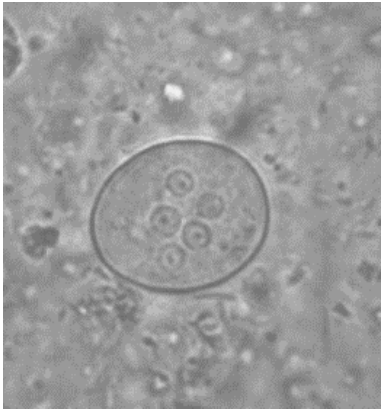

Observe a imagem a seguir.

Essa imagem foi obtida em um microscópio óptico no aumento de 400x a partir de um sedimento fecal. Na imagem, observa-se um cisto de